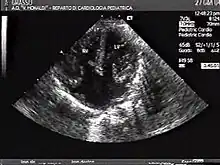

This is an echocardiography of a complete atrioventricular canal defect. There is a clear absence of the lower septum that would separate all four chambers of the heart.

Atrioventricular canal defect may be divided into partial or complete forms. In the partial form, openings between the left and right atria and improper formation of the mitral valve exist. In the complete form, there is free movement in all chambers because there is a large hole where the atria and ventricles meet, and instead of there being two valves there is one common valve.[4]